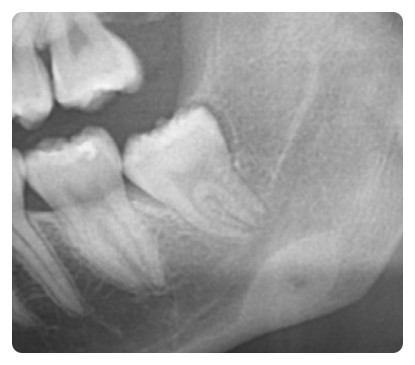

사랑니를 뽑고 난 뒤 엑스레이 사진입니다.

주변의 잇몸뼈를 전혀 건드리지 않고 깔끔하게 발치가 되었습니다.

이런 잇몸속에 숨어 있는 완전매복 발치는 치아를 통째로 뽑을 수 없기 때문에

조심해서 사랑니를 조각조각 내야 합니다.

사랑니를 뽑은 후 엑스레이 사진입니다.